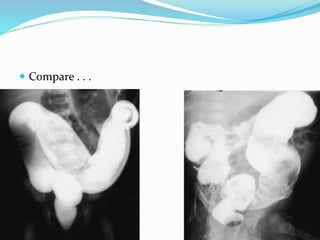

 Compare . . .

 Contrast Enema Is Diagnostic, And Also Therapeutic …

 Meconium Plug Syndrome

Meconium Plug Syndrome

 Mildest & Most Common Form Of Functional Distal

Obstruction In The Newborn.

 Obstruction Caused By Inspissated, Immobile

Meconium.

 Incidence 1 Case In 500 To 1,000 Neonates.1

 Etiology Is Unclear.

 Hint:  ContrastEnema Is Diagnostic, And Also Therapeutic …

Meconium Plug Syndrome Mildest & Most Common Form Of Functional Distal Obstruction In The Newborn.  Obstruction Caused By Inspissated, Immobile Meconium.  Incidence 1 Case In 500 To 1,000 Neonates.1  Etiology Is Unclear.